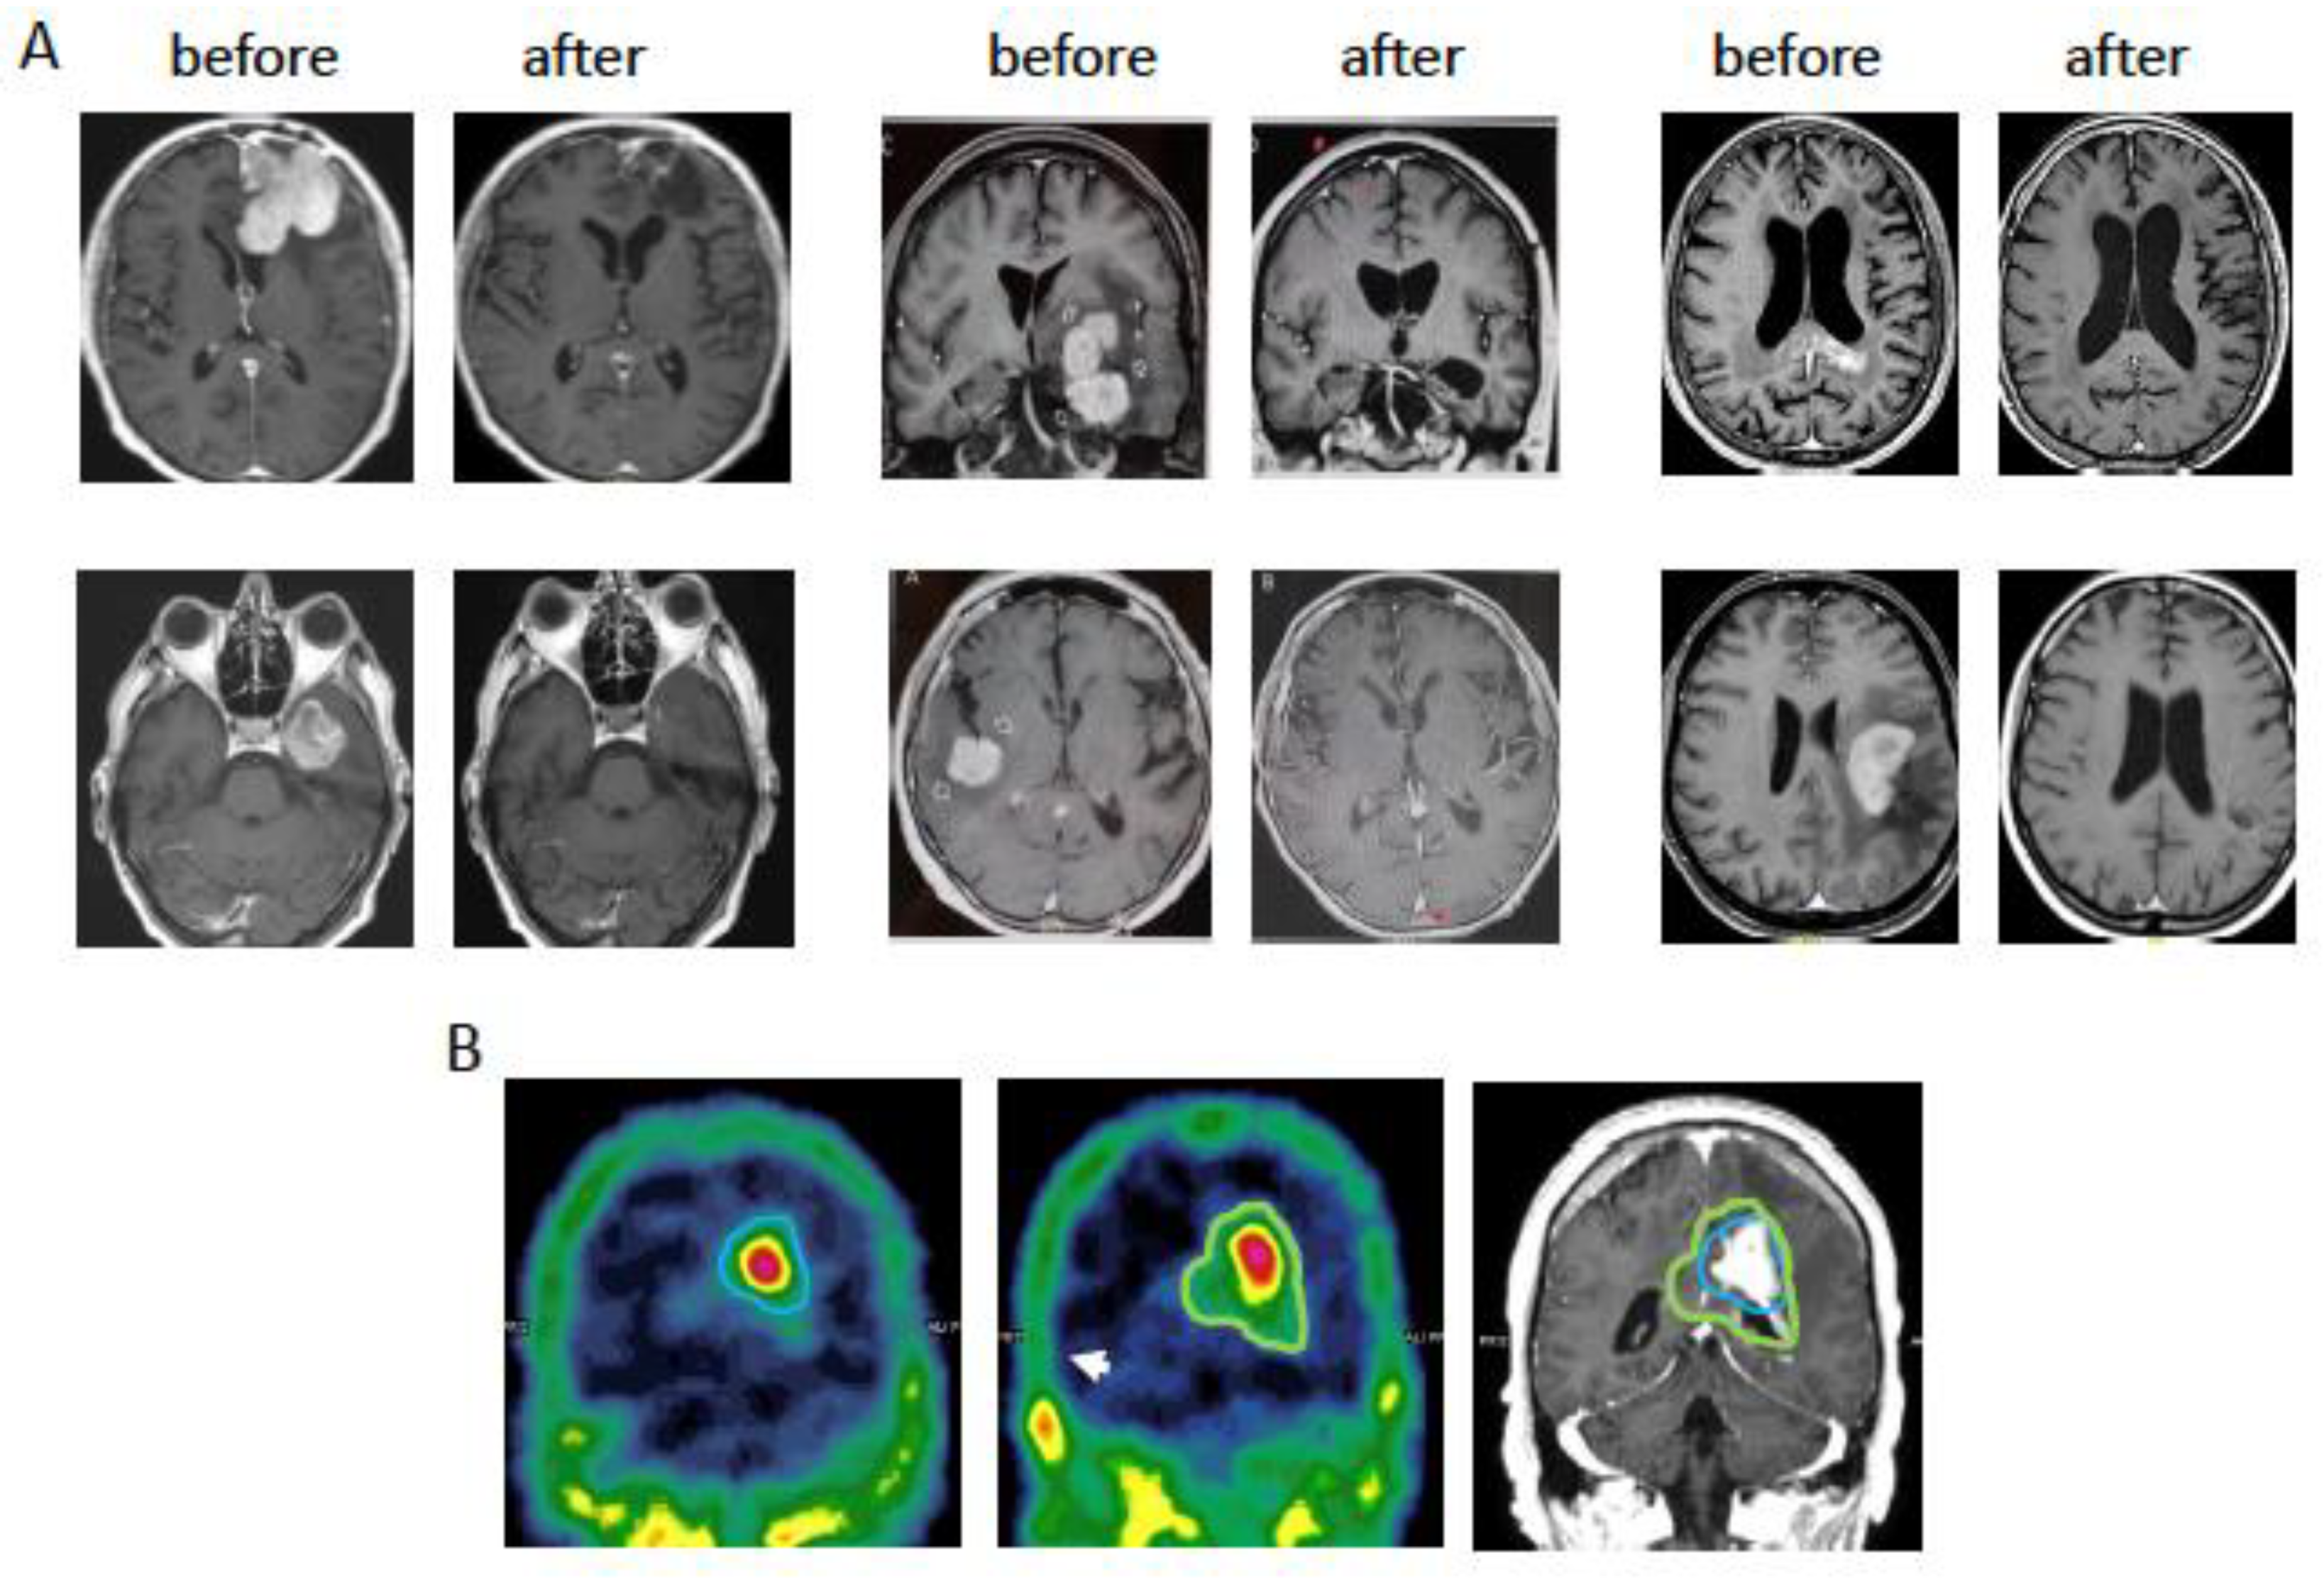

- Ferreri, A.J.M.; Calimeri, T.; Ponzoni, M.; Curnis, F.; Conte, G.M.; Scarano, E.; Rrapaj, E.; De Lorenzo, D.; Cattaneo, D.; Fallanca, F.; et al. Improving the antitumor activity of R-CHOP with NGR-hTNF in primary CNS lymphoma: Final results of a phase 2 trial. Blood Adv. 2020, 4, 3648–3658. [Google Scholar] [CrossRef] [PubMed]

- Ferreri, A.J.M.; Calimeri, T.; Conte, G.M.; Cattaneo, D.; Fallanca, F.; Ponzoni, M.; Scarano, E.; Curnis, F.; Nonis, A.; Lopedote, P.; et al. R-CHOP preceded by blood-brain barrier permeabilization with engineered tumor necrosis factor-alpha in primary CNS lymphoma. Blood 2019, 134, 252–262. [Google Scholar] [CrossRef] [PubMed]